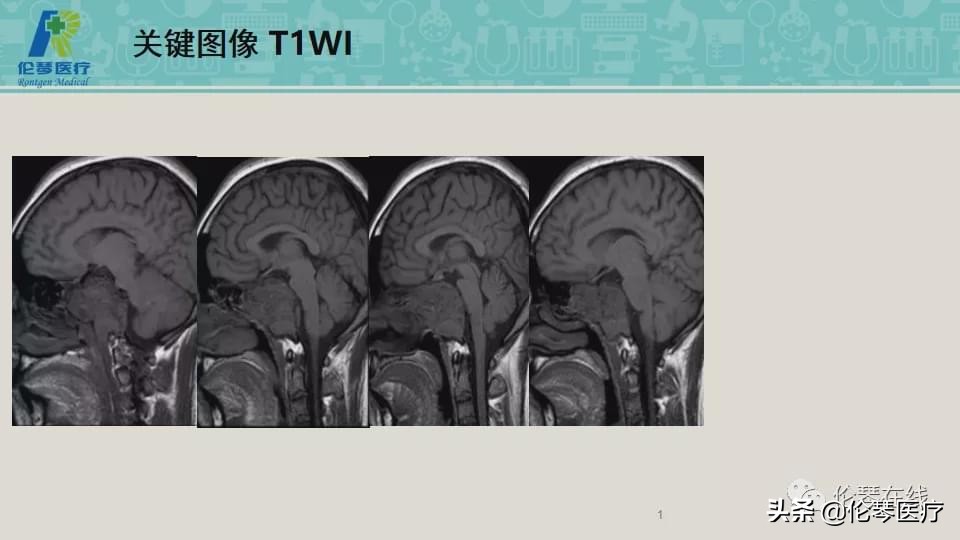

年龄:21岁

主诉:头痛,双眼内收、外展受限8个月,加重2月